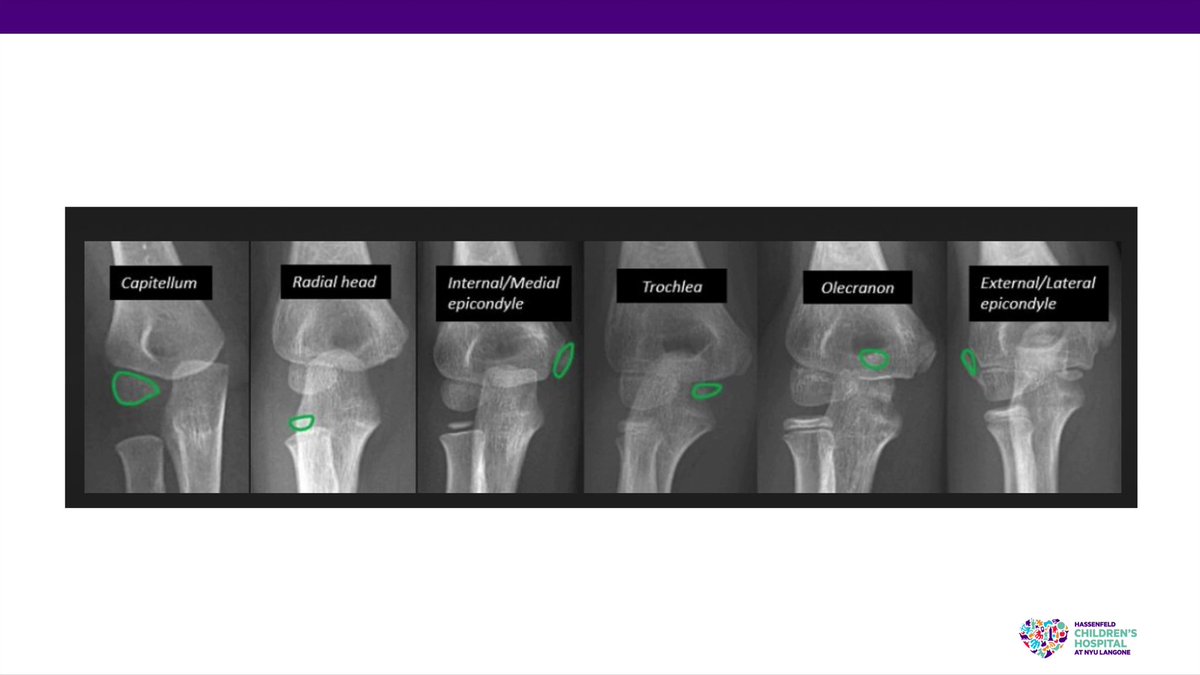

Today on #OVT watch as Mara Karamitopoulos, MD, of #NYU discusses #pediatric #xray assessment, addressing #orthopedic #trauma and #fractures topics. @DrMaraK NYU Langone Orthopedics #OVTFridays #education #orthotwitter bit.ly/3F5K4X2

Today on #OVT watch as Mara Karamitopoulos, MD, of #NYU discusses #pediatric #xray assessment, addressing #orthopedic #trauma and #fractures topics.

@DrMaraK

<a href="/nyulangoneortho/">NYU Langone Orthopedics</a>

#OVTFridays #education #orthotwitter

bit.ly/3F5K4X2